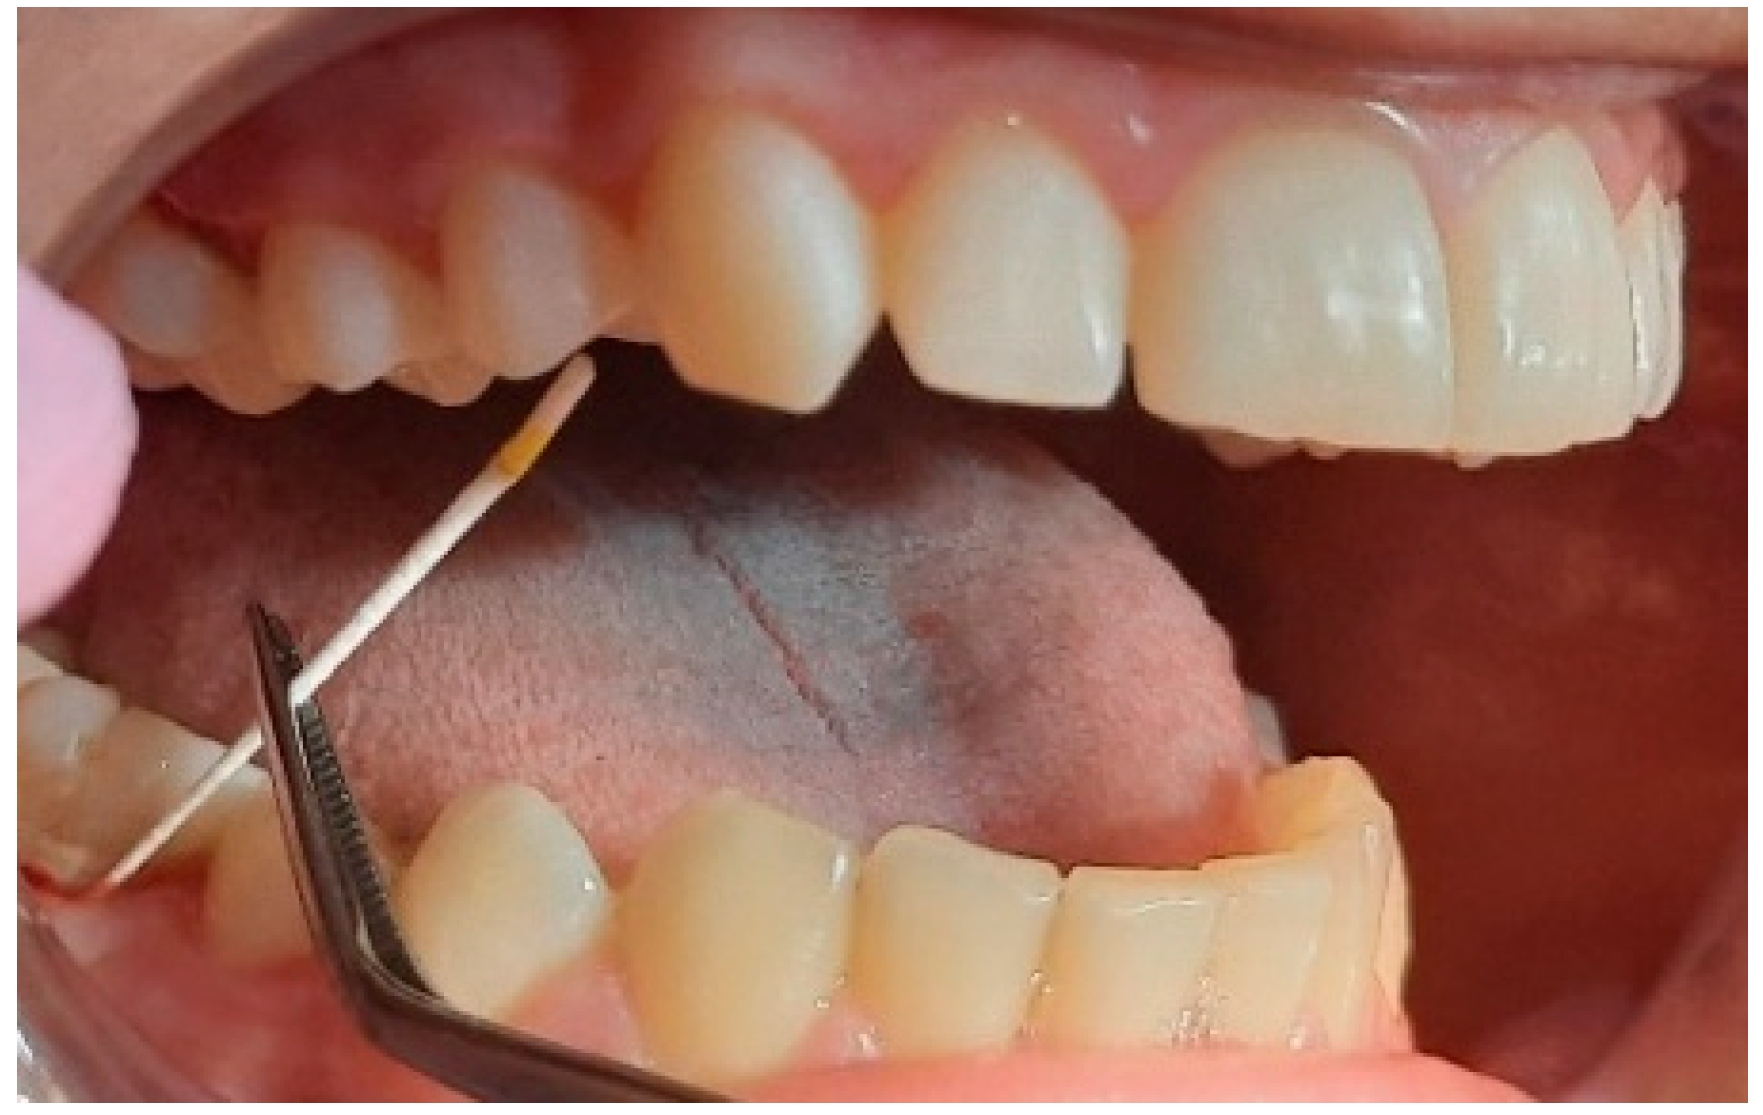

2.2. Clinical Examinations

2.3. Sampling for PCR